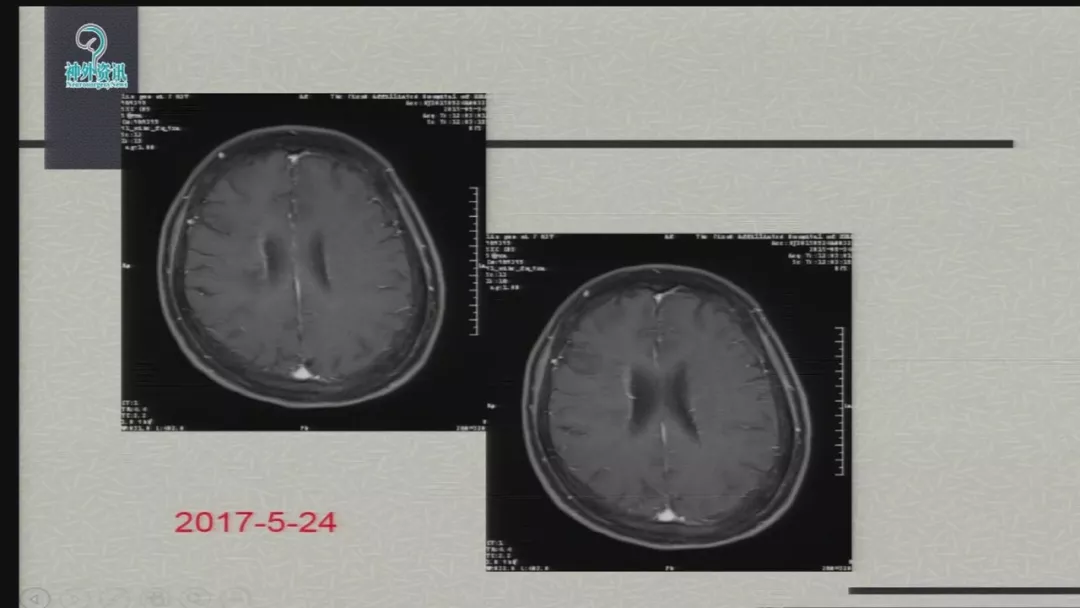

今天为大家分享的是由郑大一附院徐浩文教授在第七届全国介入医学工程大会上带来的“Neuroform EZ在ICAD治疗中的应用”精彩讲课视频和PPT,欢迎观看!(内容未经讲者审核,不当之处请与我们联系)